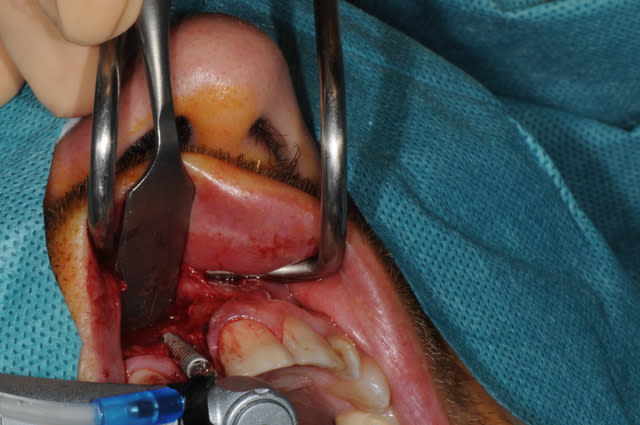

Salut, voila les photos de la chirurgie. rien d'extraordinaire , mais si certains ont des conseils, je suis preneur, j'ai la même chose à faire samedi matin

Pourriez vous me dire ce que vous utilisez pour éroder le mur palatin et éviter un axe trop vestibulaire?

Fôret Lindemann

Ça te permet de forer lattéralement

Sinon, fraise boule sur turbine chirurgicale.